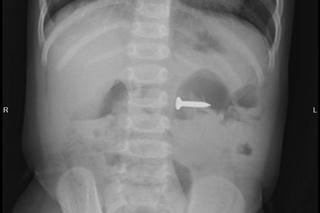

từ khóa: #đinh vít